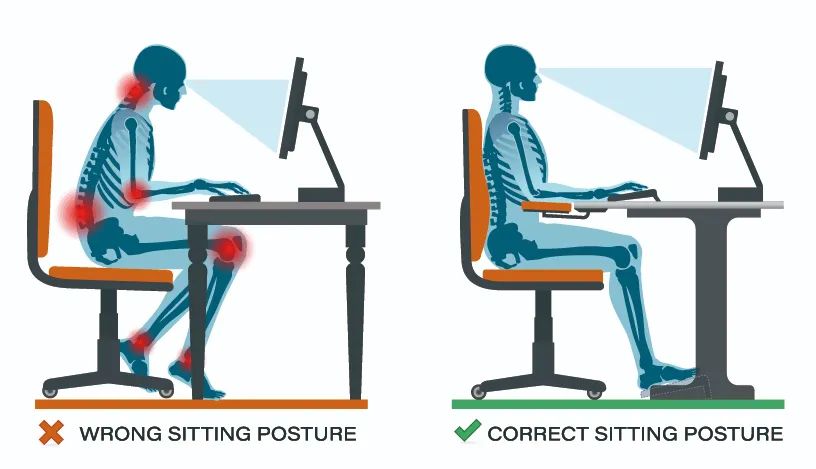

1、避免不良因素

包括纠正日常生活、工作的姿势,尽量睡硬板床,避免久坐、弯腰负重、搬东西、抱孩子等。如需重体力活动,佩戴带钢板的腰围。如工作需久坐,建议使用带靠背的座椅或在腰椎和座椅之间放一个靠垫,把腰靠上去。